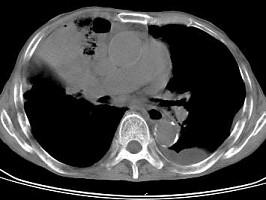

问题 男,68岁,胸闷,咳痰,咯血二月余,胸部CT如图,最可能的诊断为 ( )

选项 A、右上肺肉瘤 B、肺炎性假瘤 C、右肺中央型肺癌 D、右上肺炎 E、右上肺不张

答案 C